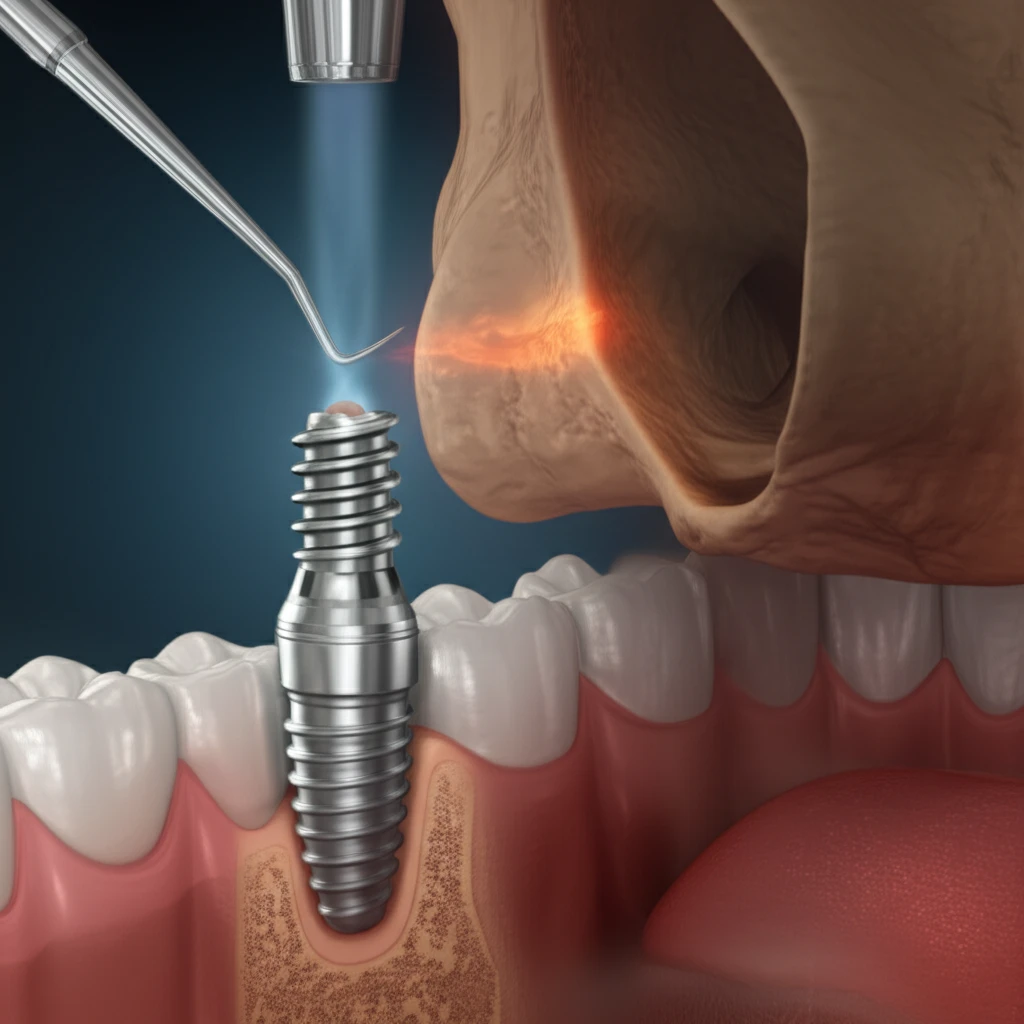

Enter graft-less sinus floor augmentation, a technique that aims to elevate the sinus floor without the need for bone grafts. This approach not only reduces invasiveness but also lowers costs, making it an attractive option for many patients. Researchers have been exploring various implant designs and surgical techniques to optimize the outcomes of graft-less sinus floor augmentation, striving for predictable and long-lasting results.

One such innovation is a new implant design specifically engineered for graft-less sinus floor elevation. This design, evaluated in a recent study, utilizes a reverse spiral flute to enhance stability and promote bone formation. The study assessed the clinical performance of this implant design when used in both lateral and crestal approaches, providing valuable insights into its efficacy and potential benefits.

The innovative implant design features several key characteristics tailored to enhance its performance in graft-less sinus floor augmentation. First, the implant has an anodized surface, which promotes osseointegration, the process by which bone grows and integrates with the implant surface. This is crucial for establishing a strong and stable foundation for the dental restoration.

- Anodized Surface: Enhances osseointegration for improved stability.

- Rounded Apex: Minimizes trauma and reduces perforation risk.

- Reverse Spiral Flute: Collects bone chips to promote new bone formation.